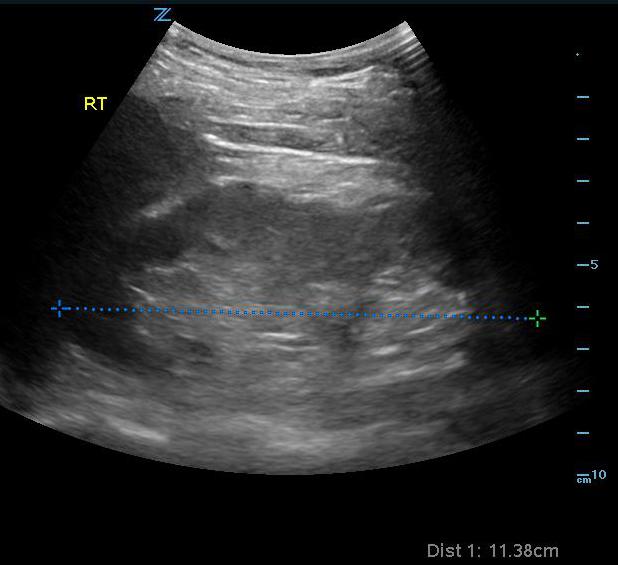

- The normal kidney will have the following characteristics:

- Bright outer covering which is made up of Gerota’s fascia and perinephric fat.

- Grainy gray periphery which is made up of the renal cortex and pyramids. Sometimes you can see the individual pyramids, but this is not always the case.

- Central bright (echogenic) area which is the renal sinus containing the calyces, renal pelvis and renal sinus fat, plus branching vessels, lymphatics and nerves.

- Length of 9-12 cm and width of 4-5 cm in the normal adult. The left kidney is often slightly larger than the right, but both should be within 2 cm of each other.

- Figure 1. Measurement of normal right kidney in longitudinal view